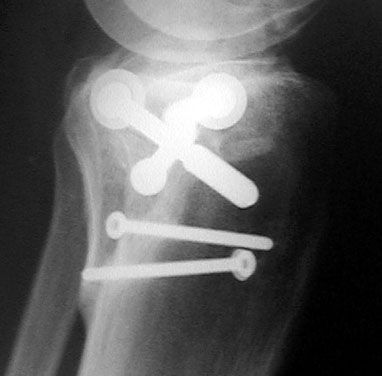

Oben: Röntgenbild vom 24. Oktober; alles klar zum Schrauben entfernen.

Oben: Röntgenbild (Seitenansicht) vom 24. Oktober 2001. Das am linken Rand des Schienbeinkopfs sichtbare, vorstehende Teil ist wieder vollständig eingewachsen. Dazu als Vergleich hier...